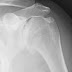

A 47 year old firefighter had bilateral ream and run procedures for incapacitating shoulder arthritis.